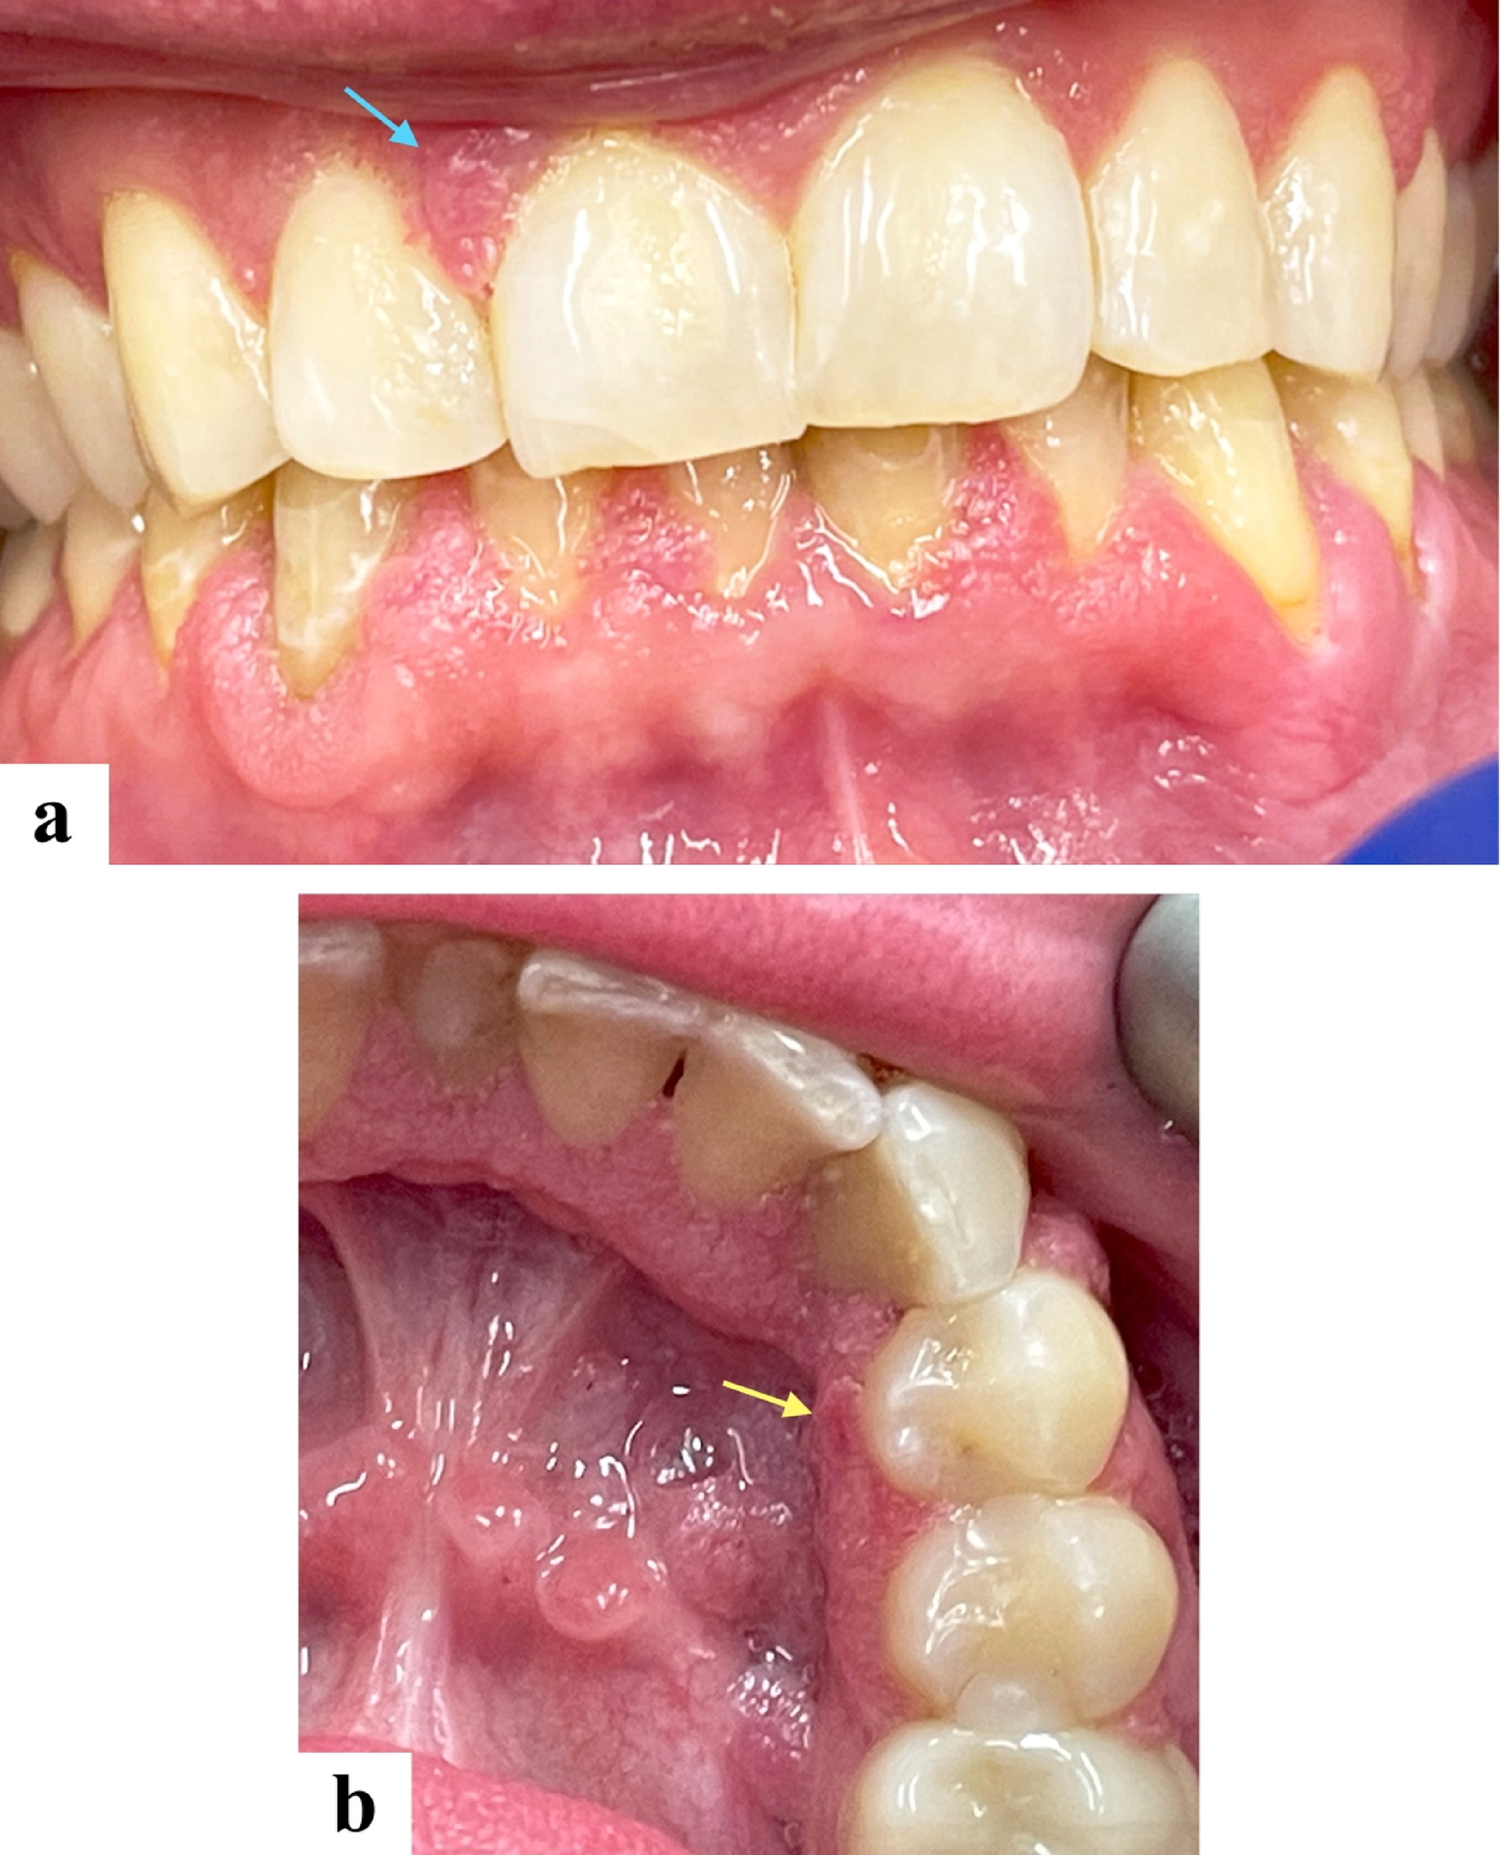

A 36-year-old male presented with numerous painless gingival lesions. He had a known history of multiple sclerosis and had been receiving fingolimod (Gilenya®, Novartis Pharmaceuticals Corp., East Hanover, NJ, USA) therapy for eight years. On intraoral examination, multiple sessile and pedunculated mucosal-colored lesions with a mildly papillomatous surface were noted along the labial aspects of both maxillary and mandibular gingiva (Fig. 1a), as well as the lingual anterior and posterior right mandibular gingiva (Fig. 1b).

Fig. 1

Clinical presentation. Multiple mucosal-colored sessile and pedunculated lesions with a mildly papillomatous surface distributed along (a) the labial gingiva of both maxilla (blue arrow) and mandible, and (b) the lingual aspect of the anterior and posterior right mandibular gingiva. The yellow arrow indicates the biopsy site